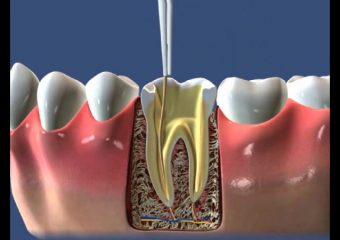

نجات دندان با درمان ریشه

نحوه نجات دندان با درمان ریشه

زمانی که داخل دندان شما (پالپ) در نتیجه پوسیدگی عمیق، اقدامات مکرر دندان، تاجهای معیوب یا ترک یا بریدگی در دندان ملتهب یا عفونی میشود، درمان ریشه یا کانال ریشه ضروری است. تروما به دندان شما همچنین ممکن است باعث آسیب به پالپ شود حتی اگر دندان هیچ تراشه یا ترک قابل مشاهدهای نداشته باشد. اگر التهاب یا عفونت پالپ درمان نشود، میتواند باعث درد یا آبسه شود. قصد داریم تا در ادامه این مطلب سایت دکتر ندا مکانیک بهترین ایمپلنت اصفهان به بررسی نجات دندان با درمان ریشه بپردازیم.

اندودنتیست پالپ ملتهب یا عفونی را برمیدارد، داخل کانال ریشه را با دقت تمیز کرده و شکل میدهد، سپس فضا را پر و مهر و موم میکند. پس از آن، شما نزد دندانپزشک خود باز خواهید گشت، که تاج یا ترمیم دیگری را بر روی دندان قرار میدهد تا از آن محافظت کرده و آن را به عملکرد کامل بازگرداند. پس از ترمیم، دندان مانند هر دندان دیگری به کار خود ادامه میدهد.

هنگامی که شما تحت درمان ریشه یا سایر درمانهای ریشه قرار میگیرید، پالپ ملتهب یا عفونی برداشته میشود و داخل دندان با دقت تمیز و ضدعفونی میشود، سپس با مادهای لاستیکی مانند به نام گوتاپرکا پر و مهر و موم میشود. پس از آن، دندان با روکش یا پرکننده برای محافظت ترمیم میشود و مانند هر دندان دیگری به عملکرد خود ادامه میدهد.